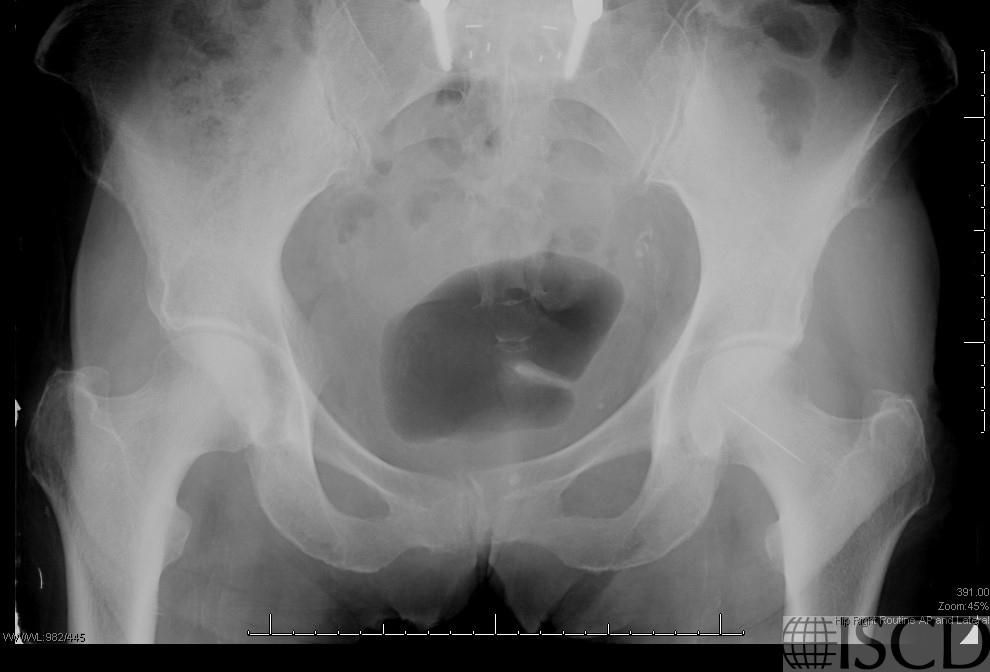

Sewing Needle over the Left Hip

This left hip DXA scan image shows a sewing needle over the left proximal femur. The contralateral femur will need to be scanned.

The needle projects over the left proximal femur on the pelvic radiograph.

This Hologic image shows a sewing needle embedded in the left buttock. Because the needle is overlying bone, it would be necessary to analyze the contralateral proximal femur. The patient remembered sitting on a sewing needle as a child, but nothing had ever been done to remove the needle.